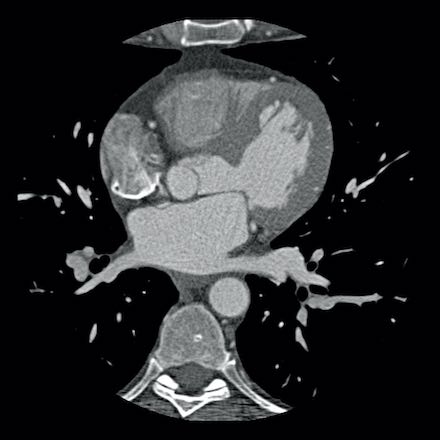

case 2 – CAD-RADS 5/P2/S

First, scroll through the CTA images.

How would you describe the findings on the coronary CTA?

The findings are:

- Stent in the mid

LAD with low-attenuation within the stent suggestive of minimal in-stent

restenosis (<25%). Non-calcified plaque distal to the stent

causing mild stenosis (25-49%). Notice bridging on a short segment in

the distal LAD. - Non-calcified

plaque in the LCX causing mild stenosis (25-49%). - Occlusion of the

proximal OM1 branch with distal filling. - Calcified and

non-calcified plaques in the proximal RCA causing mild (25-49%) stenosis. - Total plaque burden

is moderate based on SIS (four segments including proximal RCA, mid LAD, prox

LCX and OM1).

Due to the occlusion of OM1 branch and presence of the stent, this case

reads as CAD-RADS 5/P2/S, which means that this patient needs further

diagnostic workup.